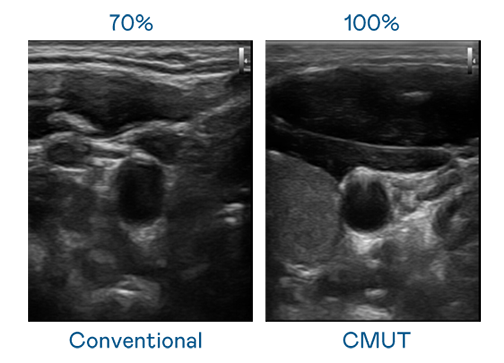

CMUT 技术是一种用电容式微机电元件来产生超音波讯号的技术。与传统 PZT 压电式技术相比,CMUT 频宽增加 30%,更宽频的超音波讯号让影像解析度大幅提升,是实现高影像品质医疗超音波扫描、促进精准医疗发展的关键技术。

超音波影像的解析度高低,首先取决于探头能发出的讯号频宽。EZPay CMUT 可提供高清晰的超音波讯号,提供高频宽、高灵敏度、影像纹理细节更高的超音波影像,协助医护人员缩短影像判读时间及利用精准的医疗影像进行诊断。